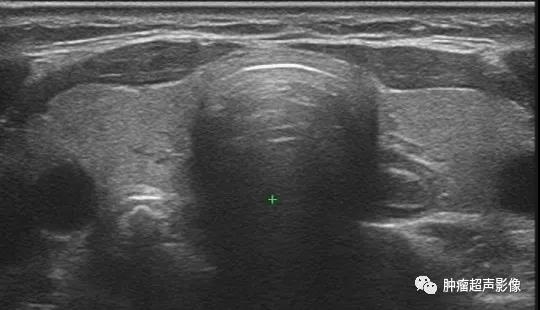

异位甲状腺(副甲状腺):甲状腺完全正常,胸骨上窝偏右侧见边界清、有包膜的不均质中等回声(类似结节性甲状腺肿),CDFI血流丰富,类似滤泡性肿瘤的血流特点。

SPECT/CT:甲状腺正常,胸骨上窝偏右侧可见放射性浓聚,考虑异位甲状腺。

FNA结果:符合良性滤泡性结节。